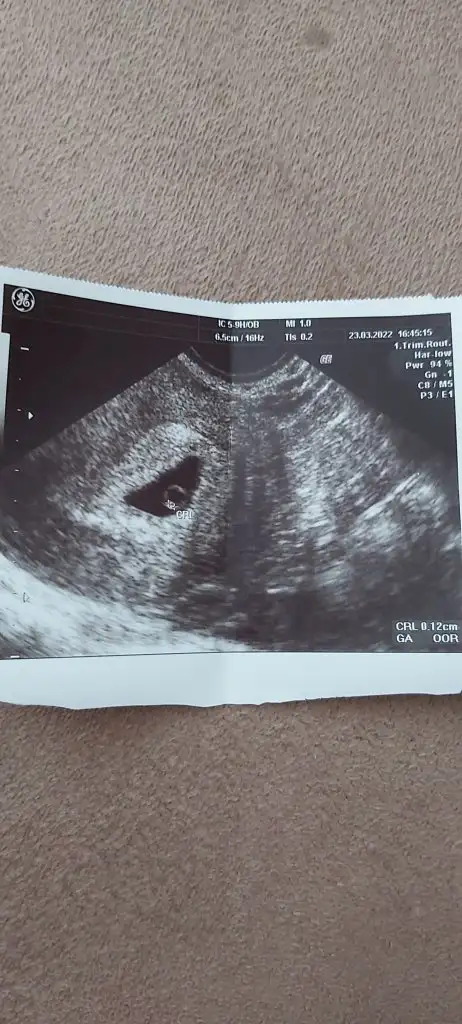

kuzum işaretli yer kesenin dışı mıCanım bana da bir tahminde bulunabilirmisin 7+2 burda karından us

Bebeğin boy ölçümü o kesenin içikuzum işaretli yer kesenin dışı mı![]()